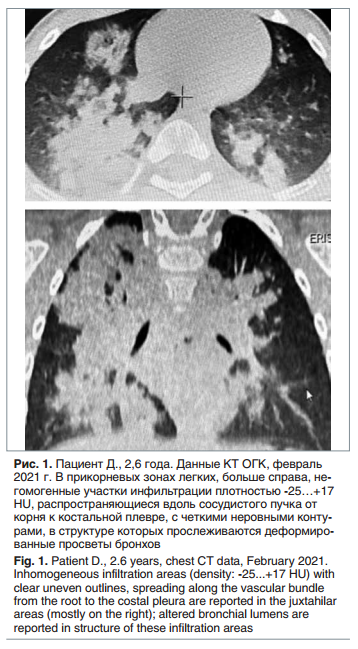

При осмотре: состояние средней тяжести по основному заболеванию. Самочувствие удовлетворительное. Температура тела 37,1 °С. Катаральных явлений нет. Кожные покровы бледно-розовые, чистые. Отмечалось умеренное тахипное, одышка при беспокойстве и плаче. Над легкими перкуторный звук не изменен. Аускультативно в легких дыхание справа ослаблено, слева пуэрильное, хрипов нет. Сатурация 98%. Частота сердечных сокращений 108 в 1 мин. Тоны сердца ясные, ритмичные. При беседе с матерью установлено, что ребенок на протяжении 6 мес. продолжает получать перорально вазелиновое масло, при этом периодически отмечались эпизоды поперхивания, которые сопровождались редким кашлем и купировались при смене ребенком положения тела (из горизонтального в сидячее). На КТ ОГК в феврале 2021 г. выявленные изменения с учетом анамнеза трактовались как признаки двусторонней ЛП (рис. 1).

Отличительной чертой представленного клинического наблюдения служит запоздалая диагностика и позднее начало целенаправленного лечения ЛП у пациента с отягощенным преморбидным фоном (тяжелая форма эпилепсии, ДЦП) и дисфагией. Несмотря на низкую общую распространенность, ЛП не является редкостью среди детей, страдающих перинатальными поражениями центральной нервной системы и тяжелыми формами эпилепсии, что связано с угнетением кашлевого и глотательного рефлексов. Продолжительный прием минеральных масел (в данном случае — вазелинового масла) значительно увеличивает вероятность развития ЛП. Компьютерная томография ОГК является «золотым стандартом» в диагностике этого заболевания. При интерпретации результатов исследования следует учитывать патогномоничные признаки: участки снижения пневматизации по типу «матового стекла», окруженные зонами консолидации, а также неоднородные участки уплотнения легочной ткани с показателями плотности в диапазоне от -30 до -150 HU, что характерно для интерстициального накопления жира. Наиболее важным компонентом этиотропной терапии при данной патологии признается полное устранение поступления липидосодержащих веществ в дыхательные пути. Без выполнения этого условия достичь положительного эффекта от лечения не представляется возможным.